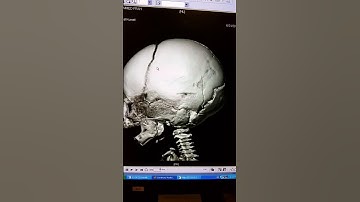

Studying open fractures in CT-scanner - Percolating fracture network (3D)